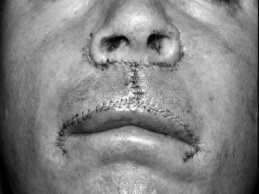

Another approach to vermillion repair for defects that are < 40% of the vermillion width is a bilateral vermillion rotation flap (Figures 2A–C).2 This flap utilizes adjacent vermillion to rotate centrally. The arcs of the rotation flap are drawn along the vermillion border with the redundant triangle of skin (dog ear) removed posteriorly. Back cuts are made at the oral commissures to permit rotation of the flaps and minimize pivotal restraint. Like the mucosal advancement flap, the bilateral vermillion rotation flap is undermined in a plane between the minor salivary glands and orbicularis muscle. This flap maintains the anterior-posterior dimension of the lip, avoids redirection of beard hairs, and decreases the risk of persistent hypoesthesia. This flap is an excellent alternative for repair of medium-sized defects in patients with less actinic damage to the adjacent vermillion.

![]() | ![]() | ![]() |

| Figure 2A: Medium-size vermillion defect prior to repair. | Figure 2B: Bilateral vermillion rotation flap completed by incision along vermillion border bilaterally to oral commissures with backcuts to permit rotation. Undermine widely deep to salivary glands on the labial mucosa and rotate and secure flaps centrally. Central tricone excised at end. | Figure 2C: Short-term healed result. |